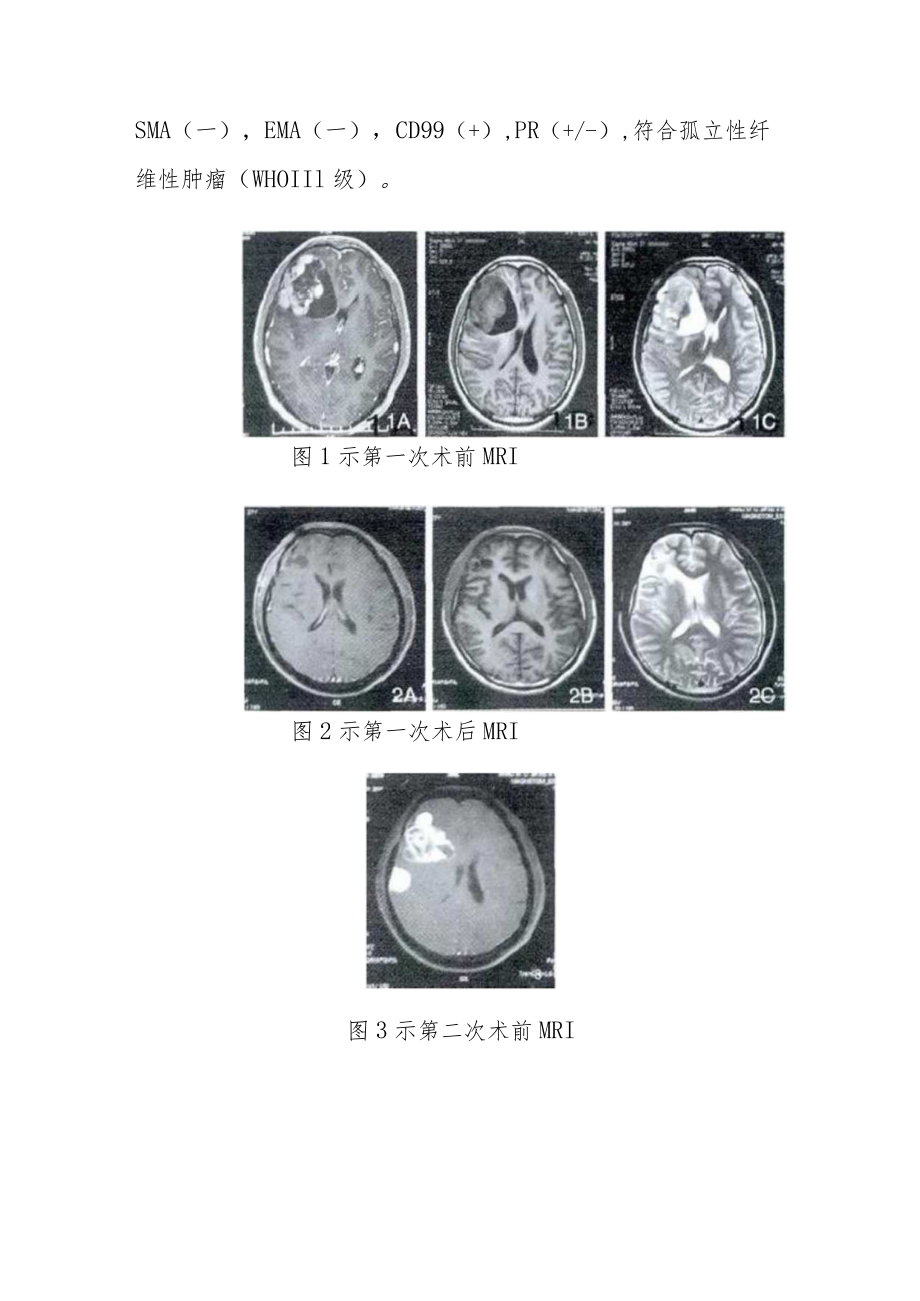

1、肿瘤科晋升副主任(主任)医师病例分析专题报告单位:*姓名:*现任专业技术职务:*申报专业技术职务:*2022年*月*日多次复发颅内孤立性纤维瘤病例分析病例:患者男,27岁,因头晕头痛不适于2011年11月初次就诊,查体无异常,头部MRl提示右额叶囊实性异常信号。术中见肿瘤灰黄色,质地不均,伴有囊变,囊液黄色,完整切除病灶。术后病理倾向于孤立性纤维瘤,免疫组化:GFAP(一),Syn(-)bcl-2(+),ki-67(10%),Vim(+),EMA(+),HMB45(一),CK(一),S-IOO(一),CgA(一),Des(一)o患者因头痛伴视力模糊一周余于2015年7月再次就诊,复查头颅MRl

2、提示右额叶异常信号,考虑孤立性纤维瘤术后复发;右侧额颗部异常信号,考虑脑膜瘤。术中见额叶病变呈灰红色,伴有囊变,囊液黄色,完整切除病变;见额题部病变基底位于凸面硬膜,边界尚清,完整切除病变。术后病理提示(右侧额叶、顶叶、颗叶)梭形细胞肿瘤,倾向于孤立性纤维腺瘤。患者因头痛头昏伴四肢乏力20余天于2016年11月就诊,查体无异常,头颅MRl提示右颗叶异常信号。再次手术术中见肿瘤肉红色,分叶状,向皮层嵌顿生长,广基粘连于大脑凸面硬膜上,连同侵蚀硬膜完整切除肿瘤。术后病理提示(右额颗叶)梭形细胞肿瘤,免疫组化:BcL-2(+),CD34(-),Ki-67(+,约30%),Vim(+),GFAP(一)

3、,S-IOO(灶+),SMA(一),EMA(一),CD99(+),PR(+/-),符合孤立性纤维性肿瘤(WHOIIl级)。图1示第一次术前MRI图2示第一次术后MRI图3示第二次术前MRI图4第二次术后MRI图5示第三次术前MRI讨论:2007年WHO中枢神经系统肿瘤分类将颅内孤立性纤维瘤归为脑膜组织肿瘤中的间叶肿瘤,而2016年新分类将其单独划为间叶性非脑膜上皮性肿瘤,但国内外关于颅内孤立性纤维瘤多为个案报道,因此关于孤立性纤维瘤的诊治研究尚需进一步研究。本病例报道显示肿瘤在头颅MRI上为平扫TlWI呈等、低信号,T2WI呈等、低及混杂信号,伴囊变及周围水肿,有占位效应,增强扫描显示肿瘤实质